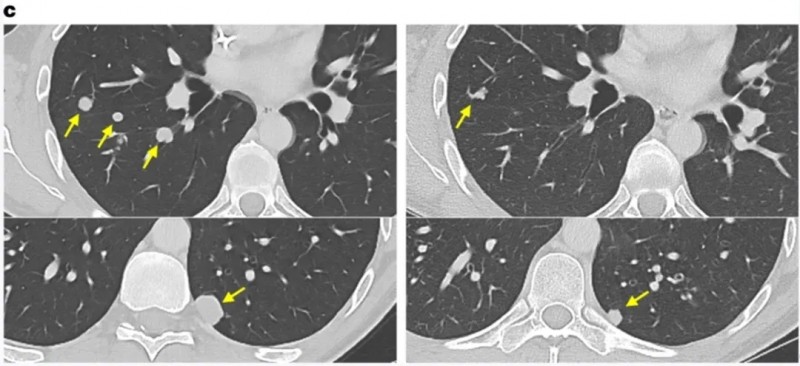

值得一提的是,一例结肠癌患者,在治疗7个月时,右肺、左肺两处结节完全消退,其余结节也缩小。

▲图源“Nat Med”,版权归原作者所有,如无意中侵犯了知识产权,请联系我们删除